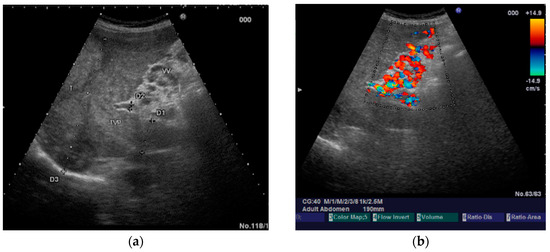

The diagnosis of PVT and PC is made by imaging procedures (transabdominal ultrasound with a Doppler or contrast-enhancing computed tomography scan, magnetic resonance imaging, or angiography in the case of therapeutic intended procedures) [1,3,12,13,14,21,29]. Transabdominal ultrasound is a reliable procedure in 60–100% of cases, with an anechoic aspect in recent cases (requiring Doppler examination or CEUS) and a hypoechoic or hyperechoic aspect in chronic cases [22,29]. Doppler examination may show an anechoic or hypoechoic thrombus and a slower (<15 cm/sec) or absent portal blood flow, and is considered the gold standard (color Doppler) for the diagnosis of PC [1], with a sensitivity and specificity of 95% (Figure 1 and Figure 2) [22]. CEUS can help the diagnosis of benign or malignant PVT, can characterize associated focal liver lesions [30], allows a better characterization of PVT [31], and also permits better detection of PC—Figure 3 and Figure 4 [32]. CT scan and MRI (Figure 5 and Figure 6) are more accurate for the evaluation of liver causes (HCC, abscesses, and other tumors) or other local causes (pancreatitis, diverticulitis, and appendicitis), and for complications (bowel infarction or perforation), and may show permeability of the portal venous system and the flow direction [1,22]. Malignant PVT has intra-thrombus arterial signals on CT, MRI, and/or CEUS, with portal vein diameter frequently 23 mm or above, and with the presence of the tumor at imaging examination (Figure 4 and Figure 6) [21].

Figure 5.

Benign portal vein thrombosis. (a) B-mode image demonstrating incomplete echogenic material within the lumen (arrowhead). The thrombus at the main portal vein affects less than 50% of the lumen. (b) No contrast uptake is observed in CEUS (arrowhead).

Figure 6.

Malignant portal vein thrombosis. (a) In standard ultrasound, the portal vein is large with an occlusive thrombus (arrowhead). (b) CEUS reveals enhancing tissue within the vessel lumen (arrowhead) in the arterial phase.

Transabdominal ultrasound with Doppler protocol (Figure 1a,b and Figure 2a,b), CT scan (Figure 3a,b), and MRI (Figure 4a,b) were used for the diagnosis in 88.9, 75.1, and 15% of cases, respectively. CEUS was used for the diagnosis in 49 cases (25.9%) but in only 29 cases was it used for the evaluation of the thrombus, and in two cases for cavernoma diagnosis (Figure 5a,b and Figure 6a,b).

CEUS detected contrast uptake in none of 10 benign thrombi (100%) and 17 of 19 (89.47%) malignant thrombi. The two unenhanced malignant thrombi were small and incomplete. All the malignant thrombi exhibited early blood flow (arterial phase, up to 30 s after contrast injection). Malignant thrombi had the same enhancement pattern as the tumor from which they originated, including rapid arterial phase hyperenhancement and slow or weak portal venous washout. In 20 cases, we visualized small hyperechoic portal vein lumen, which reflects an old thrombosis with or without PC.